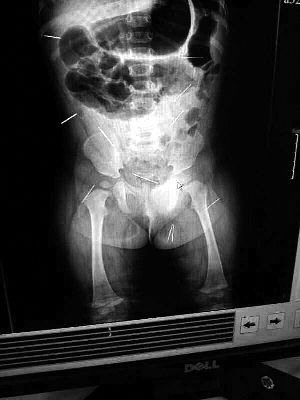

目前體內的12根鋼針多分布在孩子的臀部,一根在腹部,其余3根在胸腔附近,其中一根很接近心臟

北京晨報記者了解到,目前體內的12根鋼針多分布在孩子的臀部,一根在腹部,其余3根在胸腔附近,其中一根很接近心臟?!耙驗楹⒆犹。t(yī)生們害怕取針的時候對她造成傷害,在胸腔附近的3針可能會威脅她的生命”。